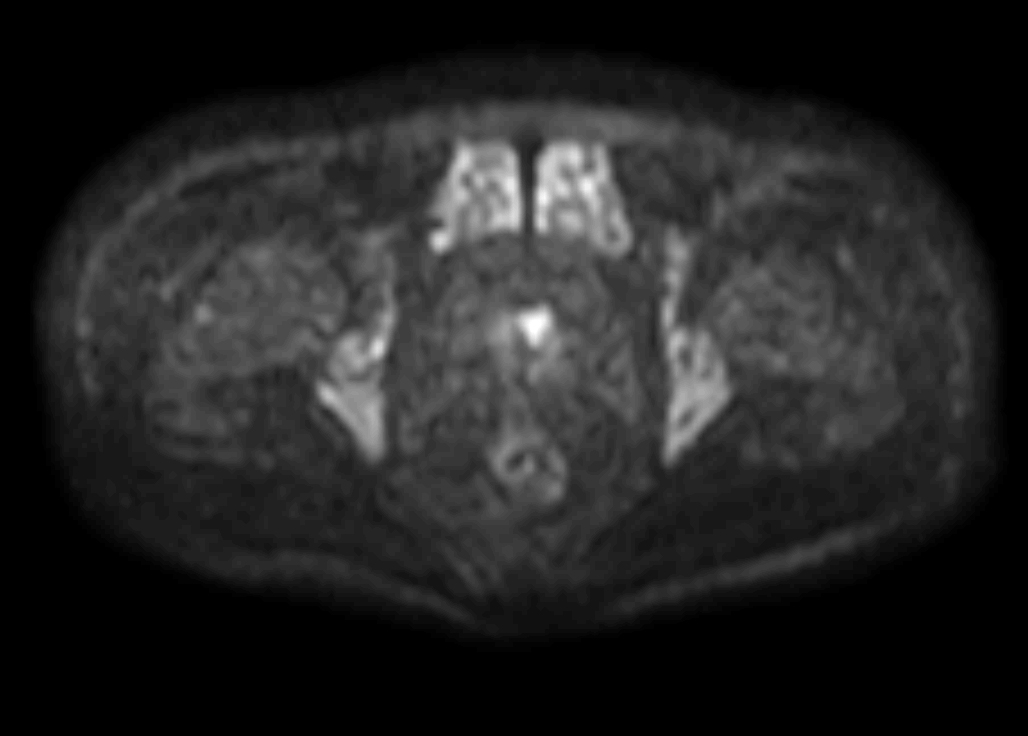

Axial DWI (b1000, ADC)